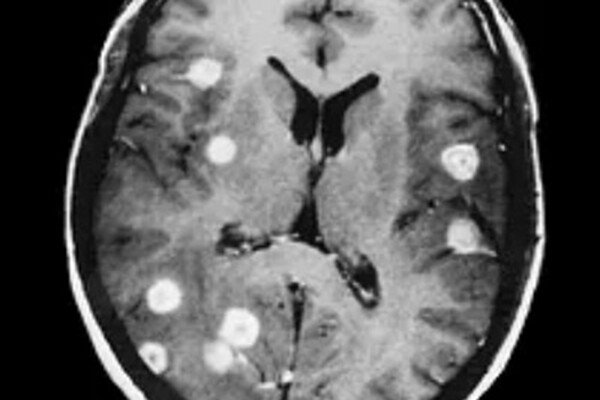

Шведские ученые из Каролинского института обнаружили, что процесс, называемый аутофагией, опосредованной шаперонами (CMA), может играть ключевую роль в подавлении метастазов рака. Открытие опубликовано в научном журнале EMBO Molecular Medicine (EMBO MM).

CMA — клеточный механизм, при котором разрушаются определенные белки. Ранее считалось, что CMA способствует росту рака, но новое исследование показало обратное. Специалисты обнаружили, что CMA может действовать как естественный защитный механизм, предотвращающий метастазирование.

Исследователи выяснили, что удаление гена LAMP2A, который контролирует CMA, привело к ускоренному росту раковых клеток и увеличению числа метастазов. Также оказалось, что CMA разрушает белки, участвующие в эпителиально-мезенхимальном переходе (ЭМП) — процессе, который помогает раковым клеткам распространяться.

Метастазы — это основная причина смертности при раке. У одного из трех пациентов метастазы уже присутствуют на момент постановки диагноза. Понимание того, как CMA может подавлять распространение раковых клеток, открывает новые возможности для разработки эффективных методов лечения.